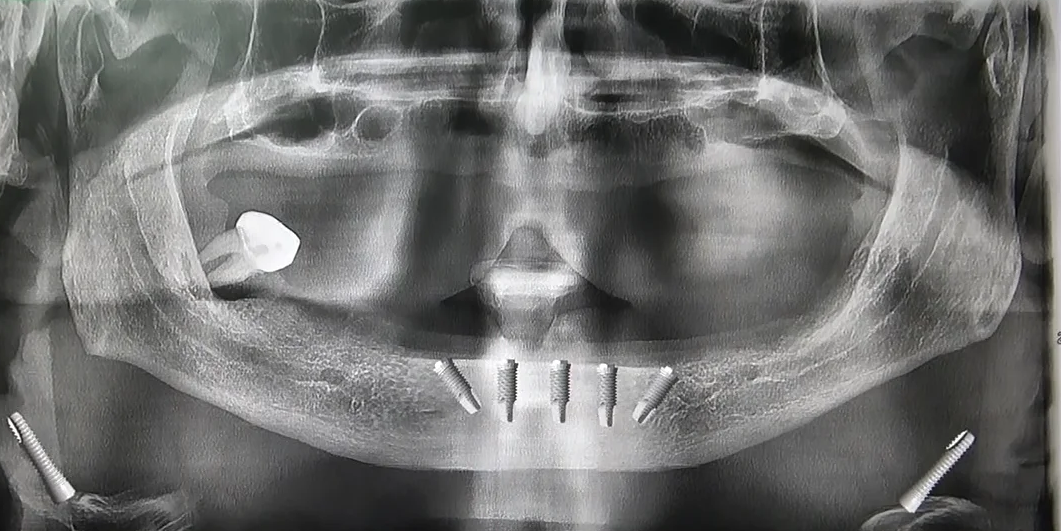

Immagini delle panoramiche prima e dopo l’intervento di implantologia dentale con tecnica del Sottoperiosteo a Griglia

Il primo passo consiste nell’utilizzare una Tac Cone Beam 3D per ottenere immagini dettagliate della struttura ossea del paziente. Questo tipo di scansione consente una visione tridimensionale precisa della mascella atrofica, permettendo ai dentisti di pianificare l’intervento in modo accurato.